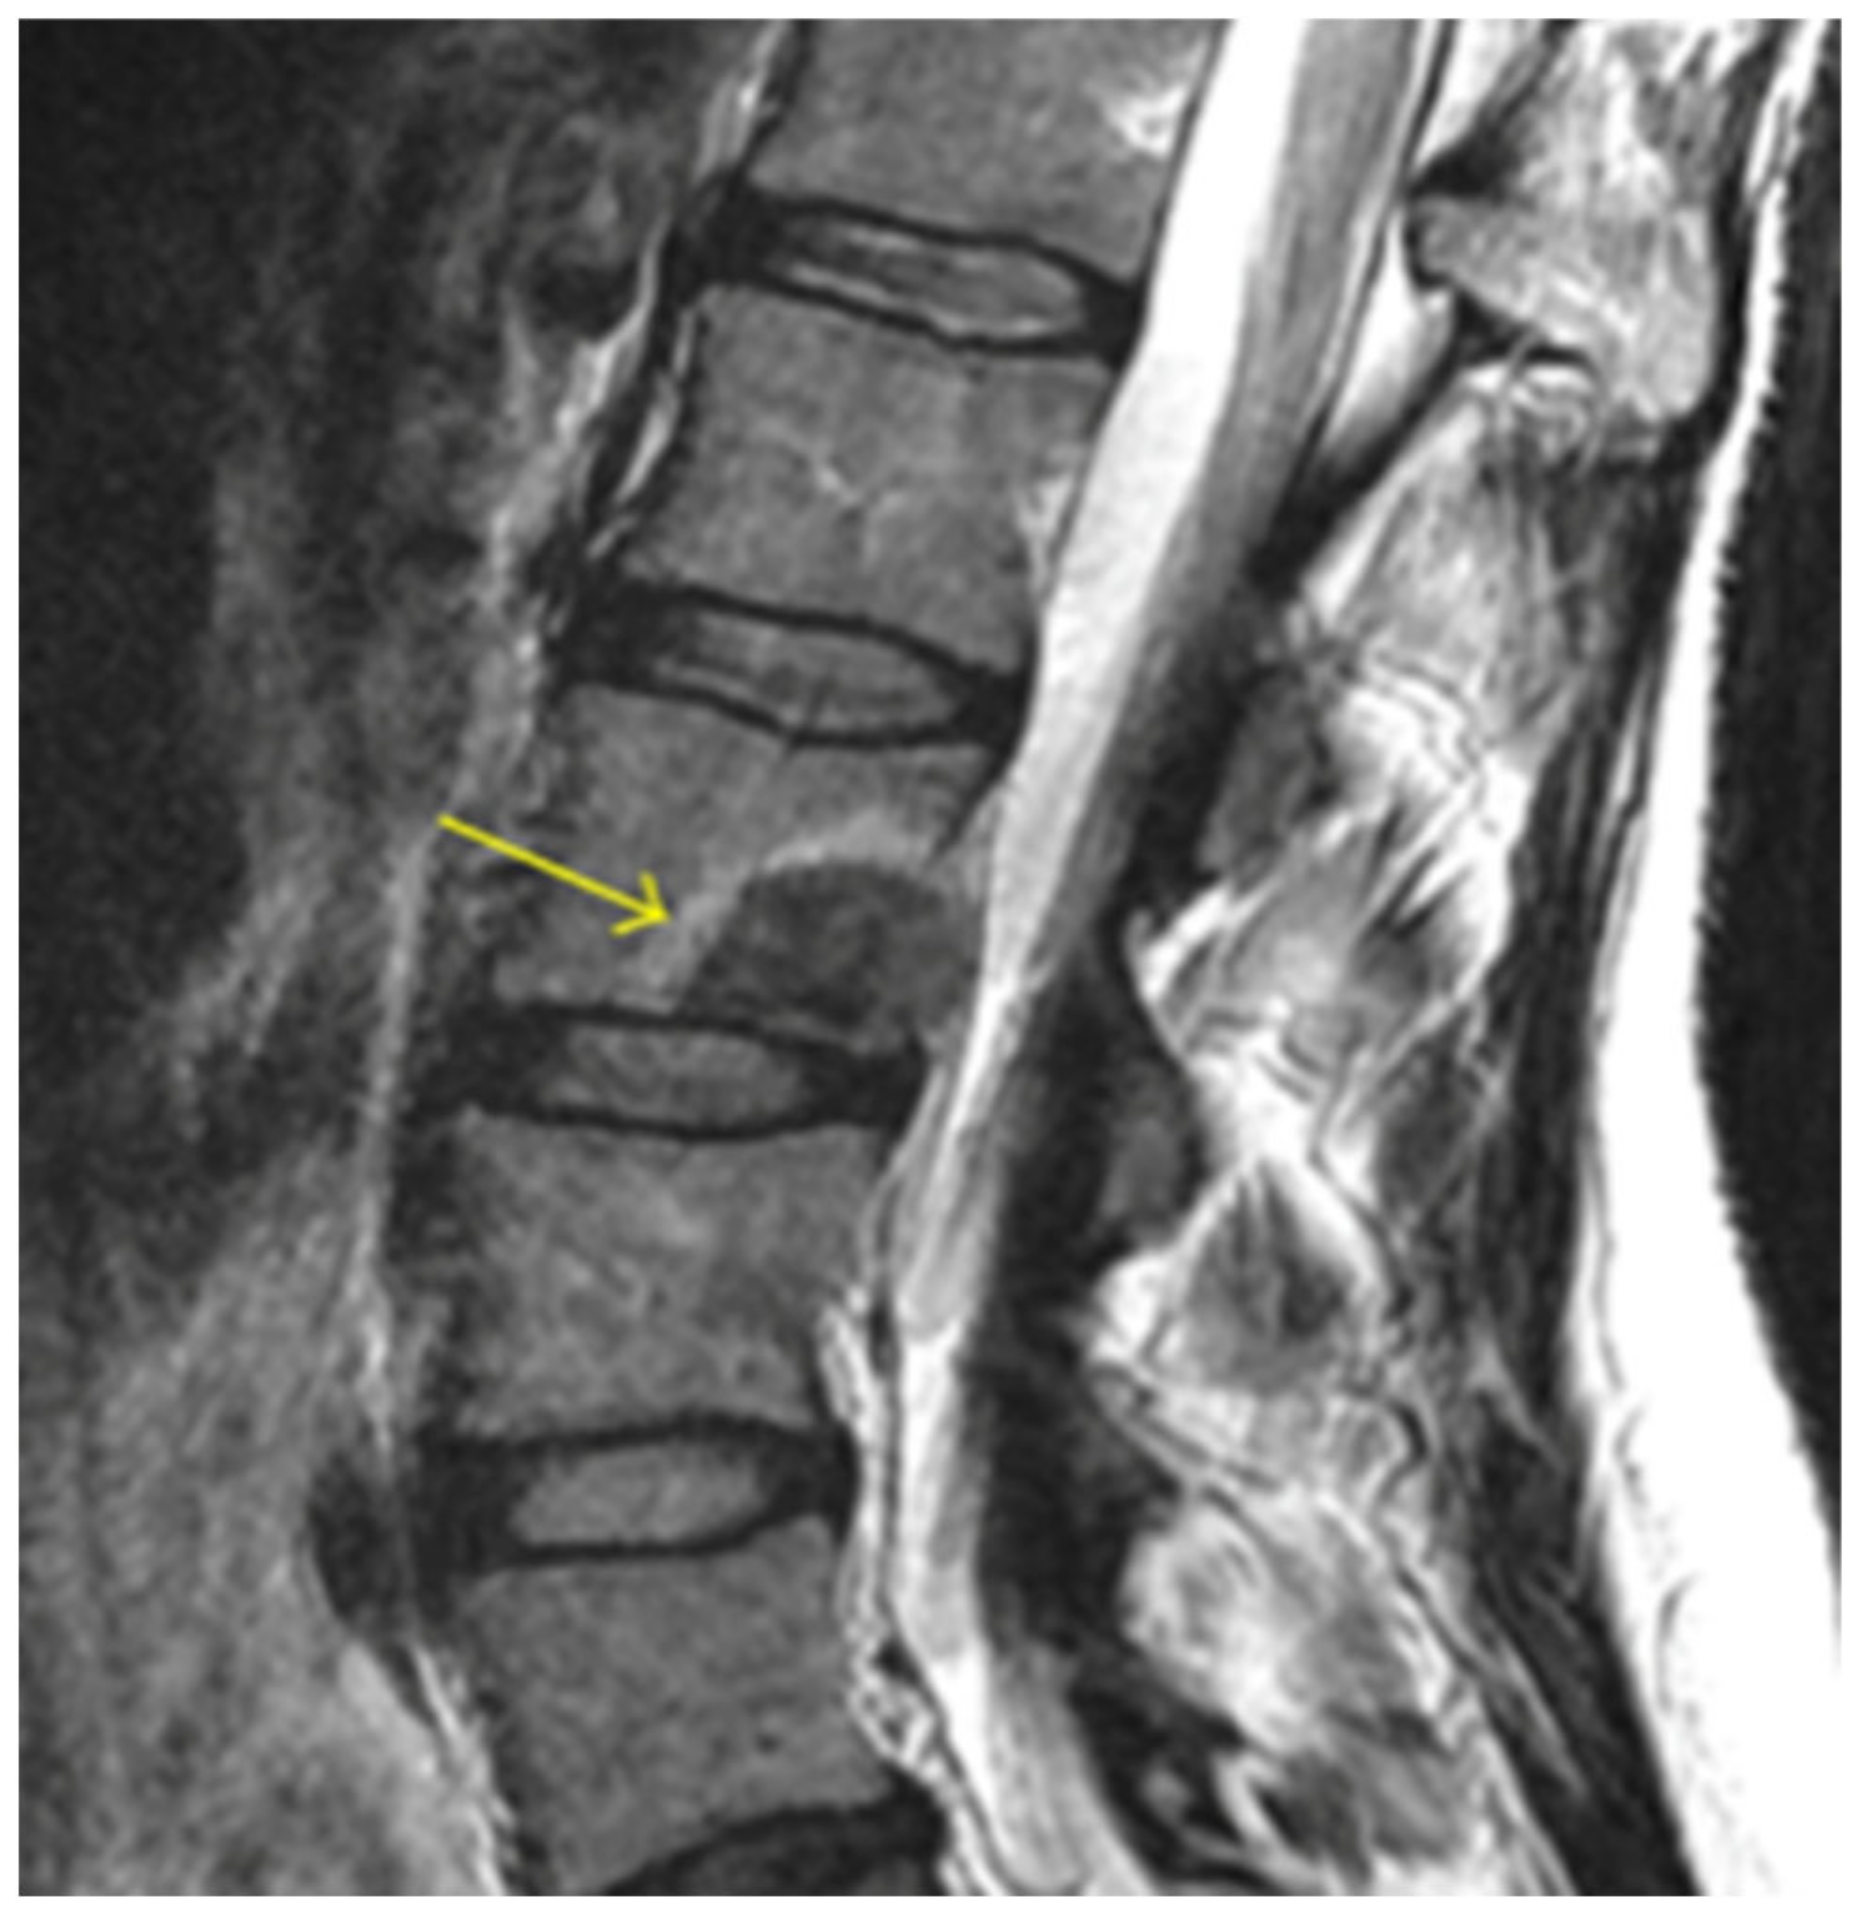

4.5. Vertebrogenic Pain

4.6. Basivertebral Nerve Ablation